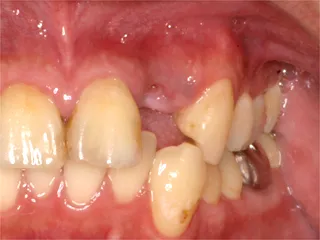

保険ブリッジ・頬側

■長所 ・安い ■短所 ・前後の歯を削り犠牲にする ※前後の歯を削り被せものをします ※抜けた歯のかわりに金属が付いています |